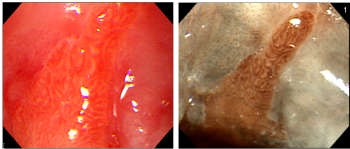

- IV.1. Endoszkópos diagnosztika és sebészet

- IV.1.1. Mi az endoszkópia?

- IV.1.2. Az endoszkópok működése